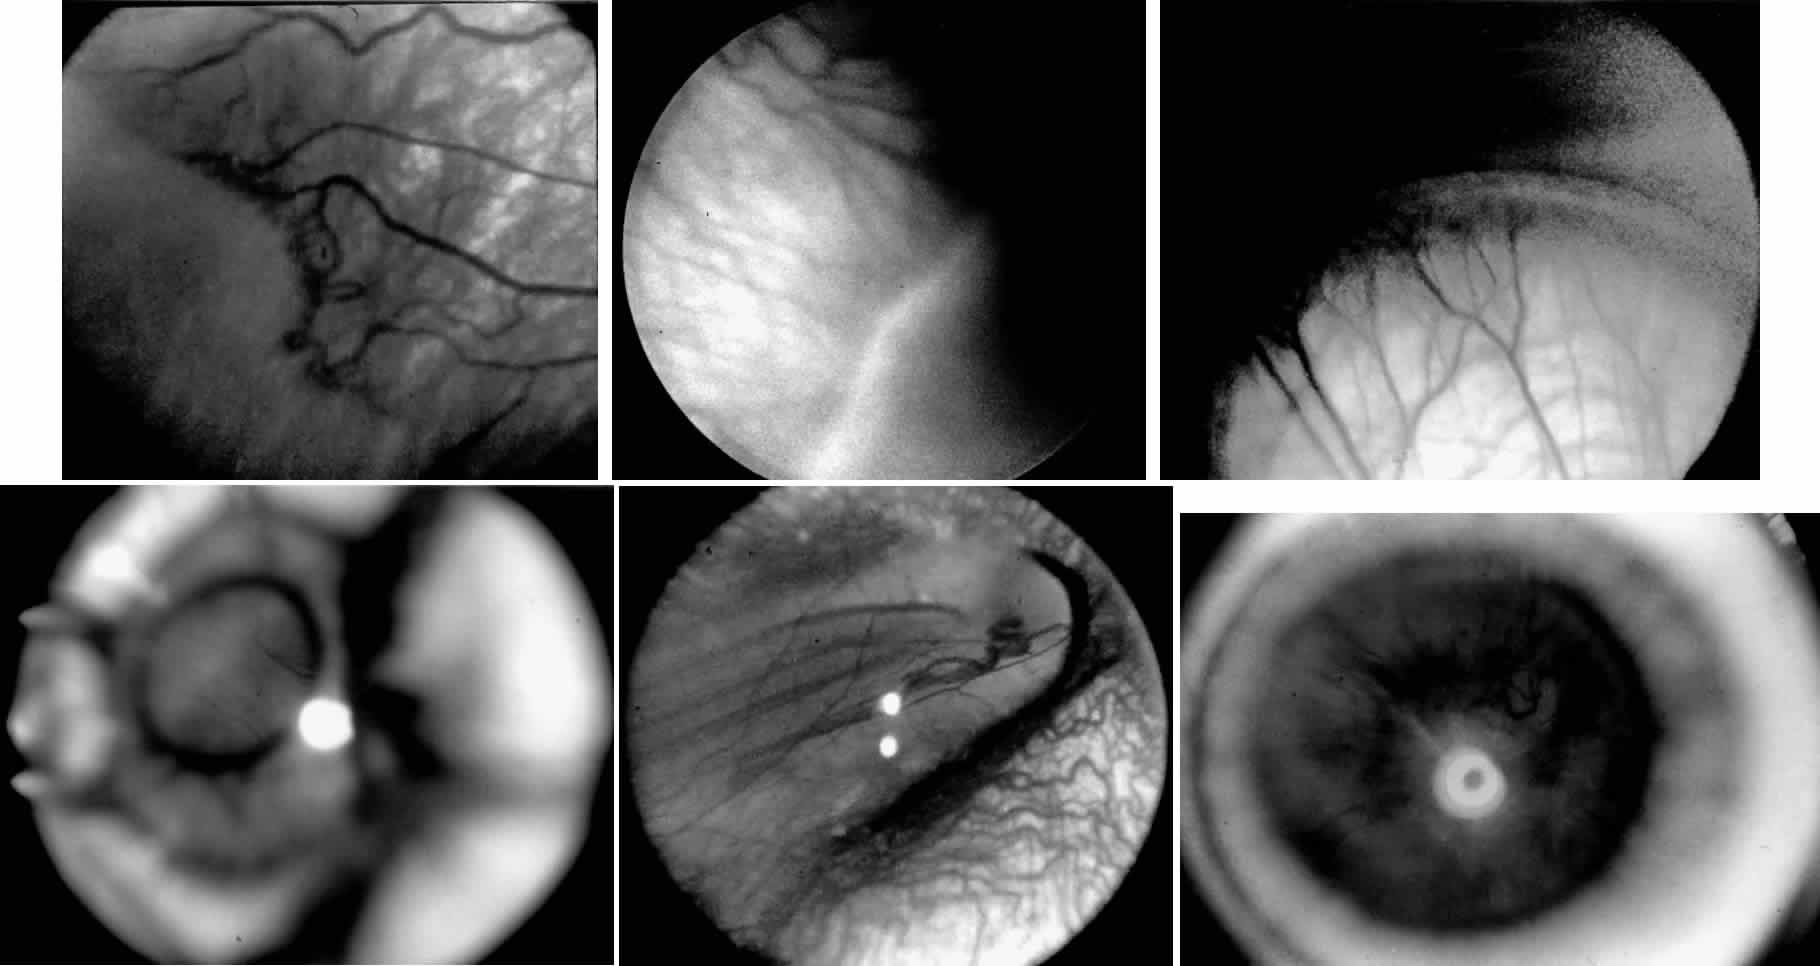

When first assessing a child's retinal detachment, one must judge the amount of effusive versus tractional detachment (Figs. 4 and 5). Scleral buckling would be considered for the child who shows a predominately effusive stage 4B detachment as opposed to a stage 4 predominately tractional detachment, for which lens-sparing vitrectomy may be recommended.24 For a child who has a great deal of retrolenticular touch, lensectomy/ vitrectomy and membrane peeling would be recommended. It appears that the “window” for lens-sparing vitrectomy may be rather brief. In one series, the postconceptual age of the lens-sparing vitrectomized eyes was 42.6 weeks, as opposed to 46.9 weeks for eyes that needed lensectomy/vitrectomy and membrane peeling. This small time difference in the postconceptual age shows the often rapid evolution of this detachment from one in which the lens is salvageable to one in which the lens is unsalvageable. This highlights the need for timely screening of eyes, identification of eyes with progressive disease, and rapid intervention.25

A child's retinal detachments progress at variable rates; thus the rate of detachment must be assessed on an individual basis. In children with RUSH disease, the eye has a very immature retina with much of the vascularized/avascular retinal juncture in zone 1. These eyes tend to progress to retinal detachment very quickly, often within 1 to 2 weeks. We have described another uncommon entity called very posterior zone 1 retinopathy of prematurity.29 In this disease, the macula is disorganized and not clearly visible. The posterior pole presents a syncytium of vessels all in zone 1. All of these eyes that we followed have gone on to have tractional retinal detachment. If there is to be any hope of vision in these patients, management requires a very rapid and broad peripheral ablative treatment followed by early vitreous surgery intervention.